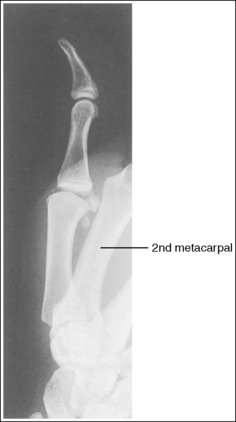

See Figure 4-27 and Box 4-10.

The second through fifth metacarpals are superimposed.

• Superimpose the second through fifth metacarpals by palpating the patient's knuckles and placing them directly on top of one another.

• Verifying a lateral hand projection. On a lateral hand projection, a true lateral wrist position, represented by superimposition of the ulna and radius, is not always accomplished when the metacarpal midshafts are superimposed. Instead, the ulna is demonstrated slightly posterior to the radius. Because of this variation, a true lateral projection of the hand should be determined by judging the degree of superimposition of the second through fifth metacarpal midshafts and not the degree of ulnar and radial superimposition. If the metacarpal midshafts are not superimposed and the fifth metacarpal is demonstrated anterior to the second through fourth metacarpals, the hand was slightly externally rotated or supinated (see Image 26). The fifth metacarpal can be identified by its length; it is the shortest of the second through fifth metacarpals. If the metacarpal midshafts are not superimposed and the second metacarpal is demonstrated anterior to the third through fifth metacarpals, the hand was slightly internally rotated or pronated (see Images 27 and 28). The second metacarpal can also be identified by its length; it is the longest.

Image 27